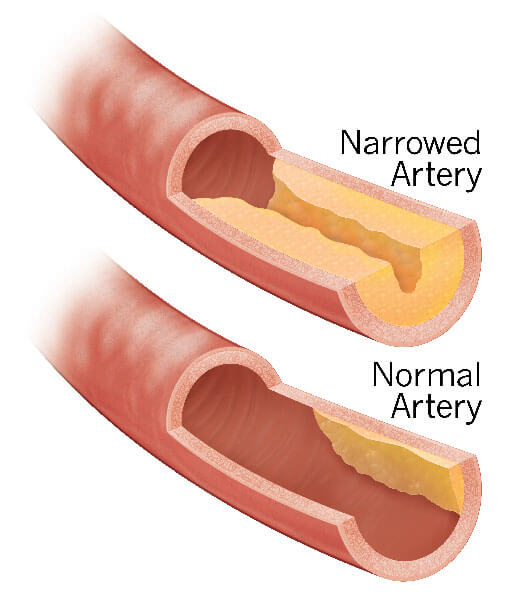

Изображения, связанные с атеросклерозом нижних конечностей и его лечением